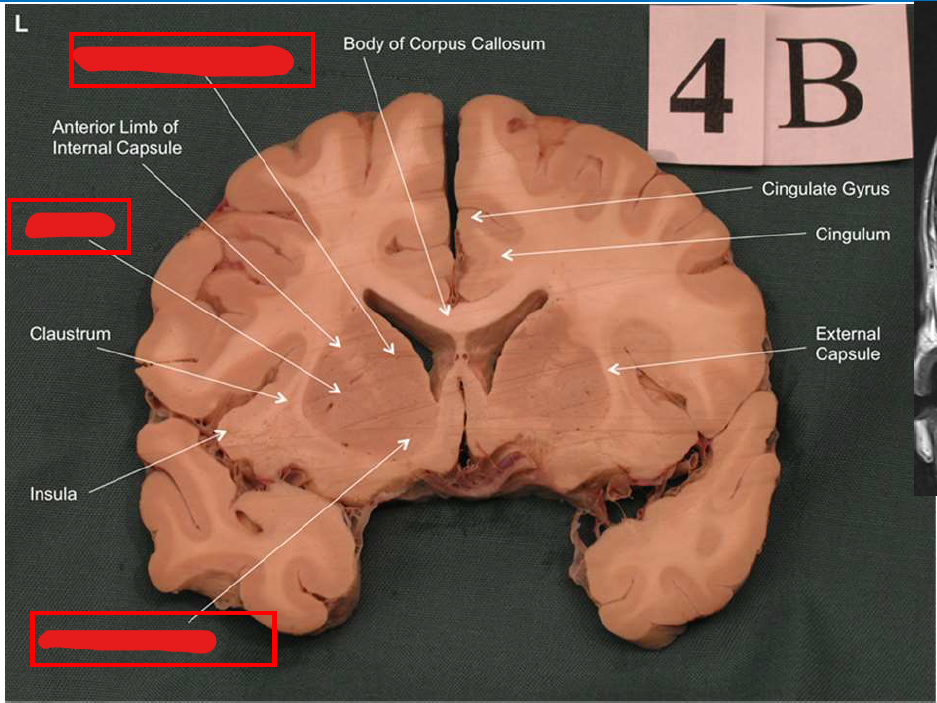

What structure is the major input to the basal ganglia?

striatum

What is the function of the nucleus accumbens (ventral striatum)?

Plays a major role in the brain's reward system, motivating us to seek pleasurable experiences.